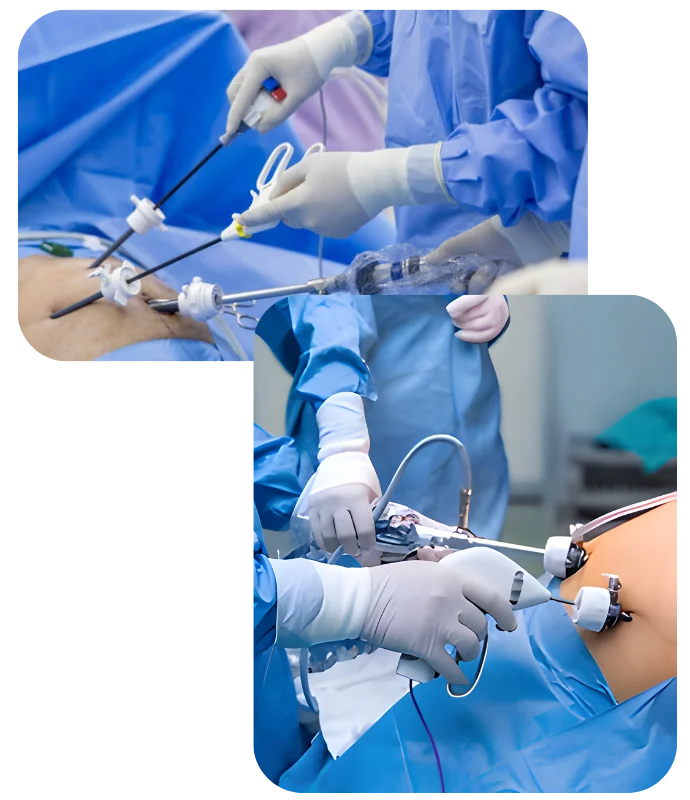

SURGICAL APPROACHES USED

Laparoscopic Oncologic Surgery

Small incisions using camera-guided instruments

High-definition visualization of cancer and surrounding tissues

Reduced pain, faster mobilization, and quicker discharge

Proven oncologic safety in selected cancers

Robotic-Assisted Cancer Surgery

Enhanced precision, flexibility, and 3D visualization

Greater control in complex or confined surgical areas

Improved accuracy during tumor dissection and reconstruction

Faster recovery with minimal impact on surrounding tissues